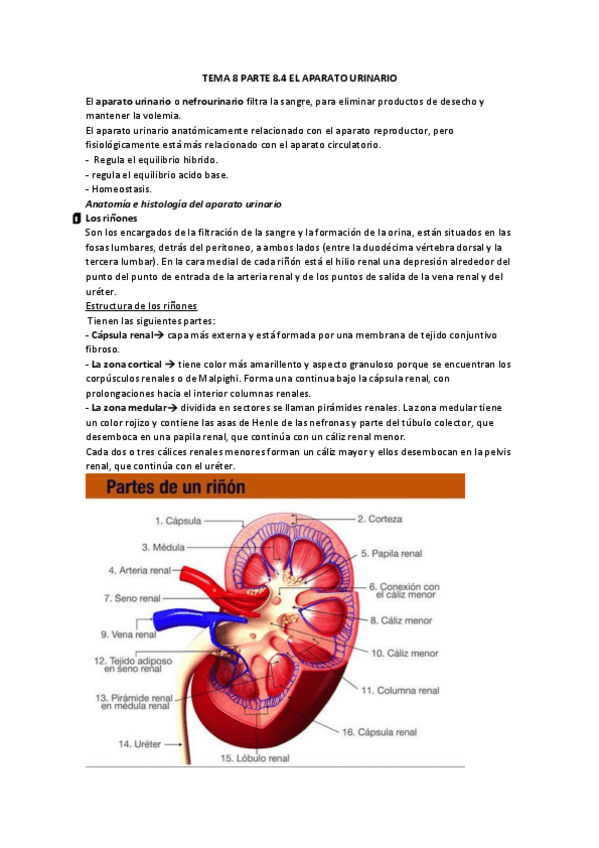

He publicado nuevos apuntes de Fisiopatología general: EL-aparato-urinario.pdf